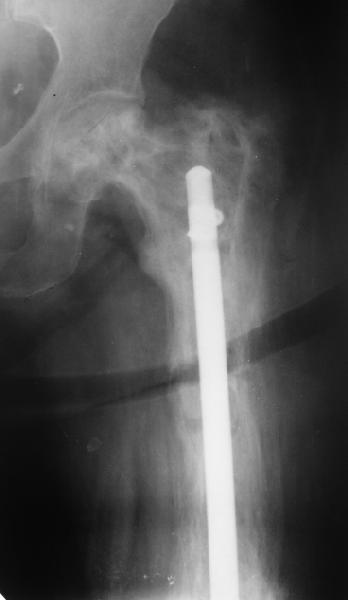

бывали ли у кого-нибудь такие случаи Уважаемые коллеги, вчера прооперировал женщину 60 лет с болезнью Педжета, переломом верхней трети бедра. Выявлена в августе этого года, сломала три дня назад от небольшого усилия. Из сопутствующих болезней лейкоз, сахарный диабет. Бывали ли кого-нибудь такие случаи, чем это все заканчивалось?

Пациент 82 лет, поступил через 5 мес. с несросшимся переломом после открытого интрамедуллярного остеосинтеза. Выполнили реостеосинтез стержнем 12 мм. ( мах. доступного нам в 2003 г.) Через 4 мес динамизация. В течении 2х лет сращения нет, тем не менее конечность опорна (ходит с тростью). От очередного реостеосинтеза отказались из-за сопутств. патологии.

Еще один пример. Пациентка с юга России, прислала рентгенограммы через год. На сегодня прошло 2 г. 8 мес. после операции. Несмотря на не очень убедительный процесс сращения, пациентка ходит. Учитывая остеопороз при Педжете, решили, что динамизировать вообще не нужно.

При переломах на фоне болезни Педжета металлоконструкция часто служит эндопротезом, несущим нагрузку. Динамизация индивидуальна,- по рентген-динамике. Основной упор- на медикаментозную терапию- см. канд. дисс. Колондаева А.Ф.

Стержень можно было бы поставить подлиннее.

Анатолий Леонидович Баранецкий совершенно прав. Сращения ждать надо очень долго (несколько лет). Главное - гвоздь попрочнее и потолще. Раньше использовали мощный 4-гранный штифт ЦИТО. Можно и гвоздь с блокированием (блокировать только с одной стороны) - но ни в коем случае не полый. И ходить с тростью. Сейчас в России зарегистрирован очень хороший препарат (с декабря 2006 г.) - Акласта, по 100 мл - обычно хватает 1 (реже двух) инфузии для полной ремиссии (в Белоруссии он появился даже раньше, чем на Украине и в Россиии). Немного хуже Аредия, ее надо в сумме 180-240 мг, полная эффективность 84%. Все в\в кап. бисфосфонаты вызывают выраженную гипокальциемию. Поэтому приходится назначать по нескольку лет альфакальцидол под контролем Са крови (каждые 3-6 мес). Сперва по 6-8 капсул (капель), т.е 1,5-2,0 мкг, затем через 2-4 месяца - по 0,5-0,75 мкг. Препараты Са по 1-2 гр. в день, очень долго.